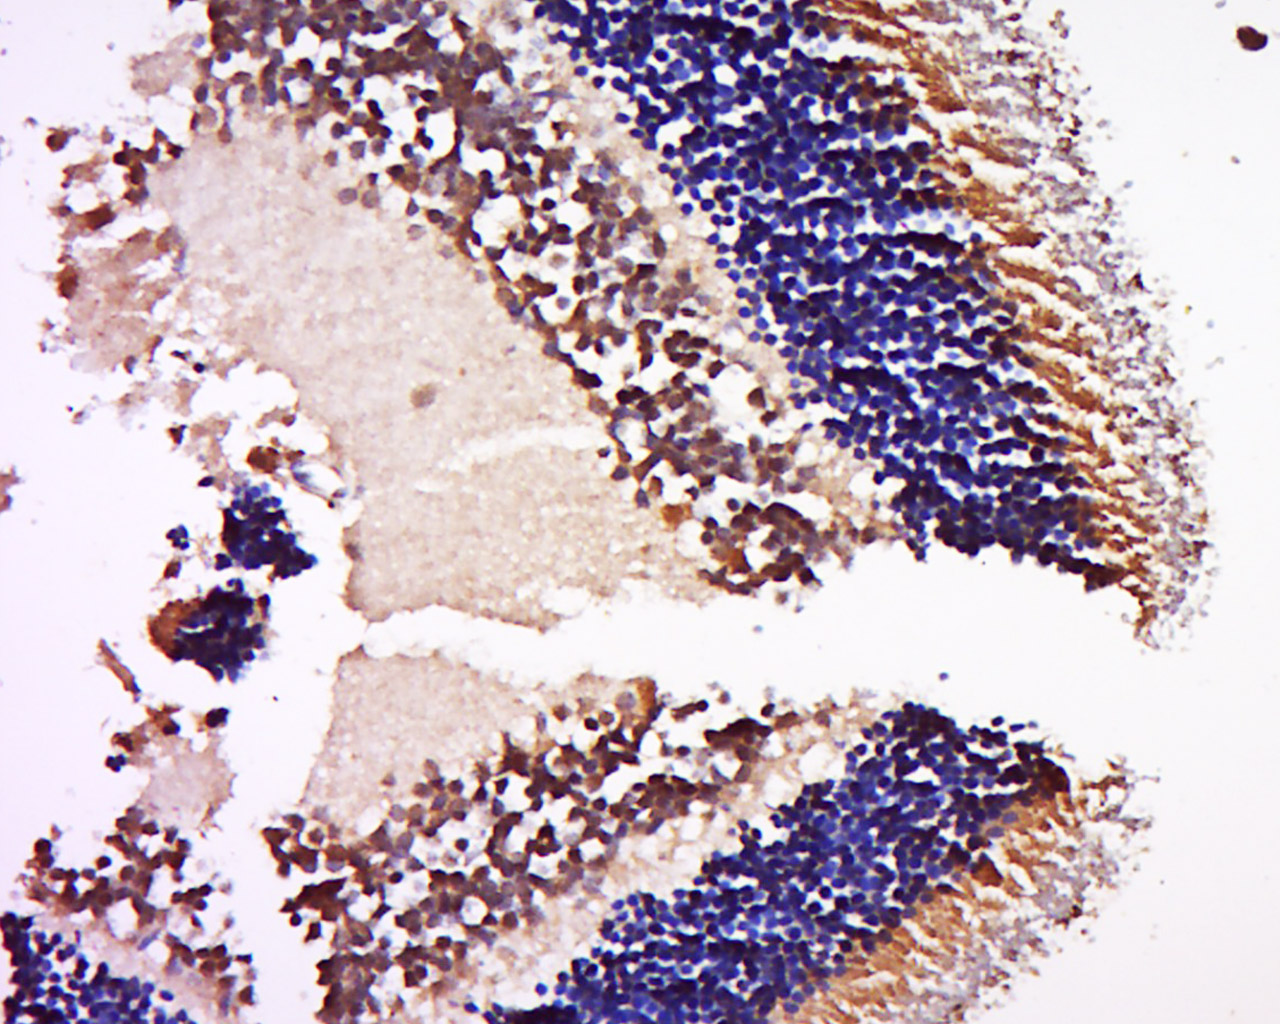

Tissue/cell: Rat eye tissue; 4% Paraformaldehyde-fixed and paraffin-embedded; Antigen retrieval: citrate buffer ( 0.01M, pH 6.0 ), Boiling bathing for 15min; Block endogenous peroxidase by 3% Hydrogen peroxide for 30min; Blocking buffer (normal goat serum,C-0005) at 37∩ for 20 min; Incubation: Anti-NRL Polyclonal Antibody, Unconjugated(bs-19351R) 1:500, overnight at 4∑C, followed by conjugation to the secondary antibody(SP-0023) and DAB(C-0010) staining